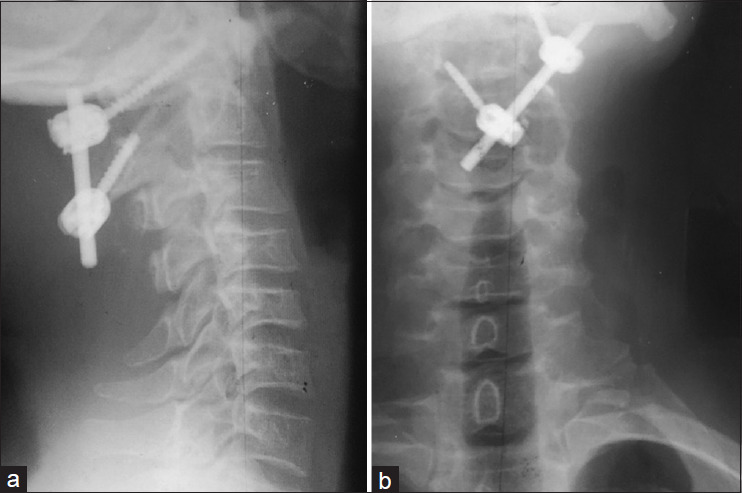

The shunting system has been generally recognized for the treatment of syringomyelia. However, recent publication has documented the role of atlantoaxial stabilization in the treatment of this condition. The objective is to present a case report highlighting our experience in the management of syringobulbia and syringomyelia in an adult male. We present a 45-year-old male who presented with an inability to walk with associated bladder and bowel symptoms. Neuroradiological studies of the brain and the whole spine revealed an extensive syringomyelia extending from the medulla oblongata to the T12 thoracic spinal level. There was no obvious focal mass lesion or bony lesion, and there were no anatomic features suggestive of Chiari I malformation. A management decision was challenging in this case. Atlantoaxial stabilization was considered based on Atul Goel's philosophy that the basic pathology in syringomyelia is C1/C2 instability, and that treatment is C1-C2 fixation. Intraoperative findings confirmed atlantoaxial instability from the direct bone handling during the procedure. There was immediate postoperative improvement in his motor function, which remained sustained, with free and brisk active mobilization at 3 months follow-up. Neuroimaging performed at 14 month's postsurgery revealed a reduction in the size of the syrinx cavity. This single and first experience of atlantoaxial stabilization for the treatment of syringomyelia in our environment may support the assertion by Goel that atlantoaxial instability is the pathology in syringomyelia, and atlantoaxial fixation should be a therapeutic consideration.